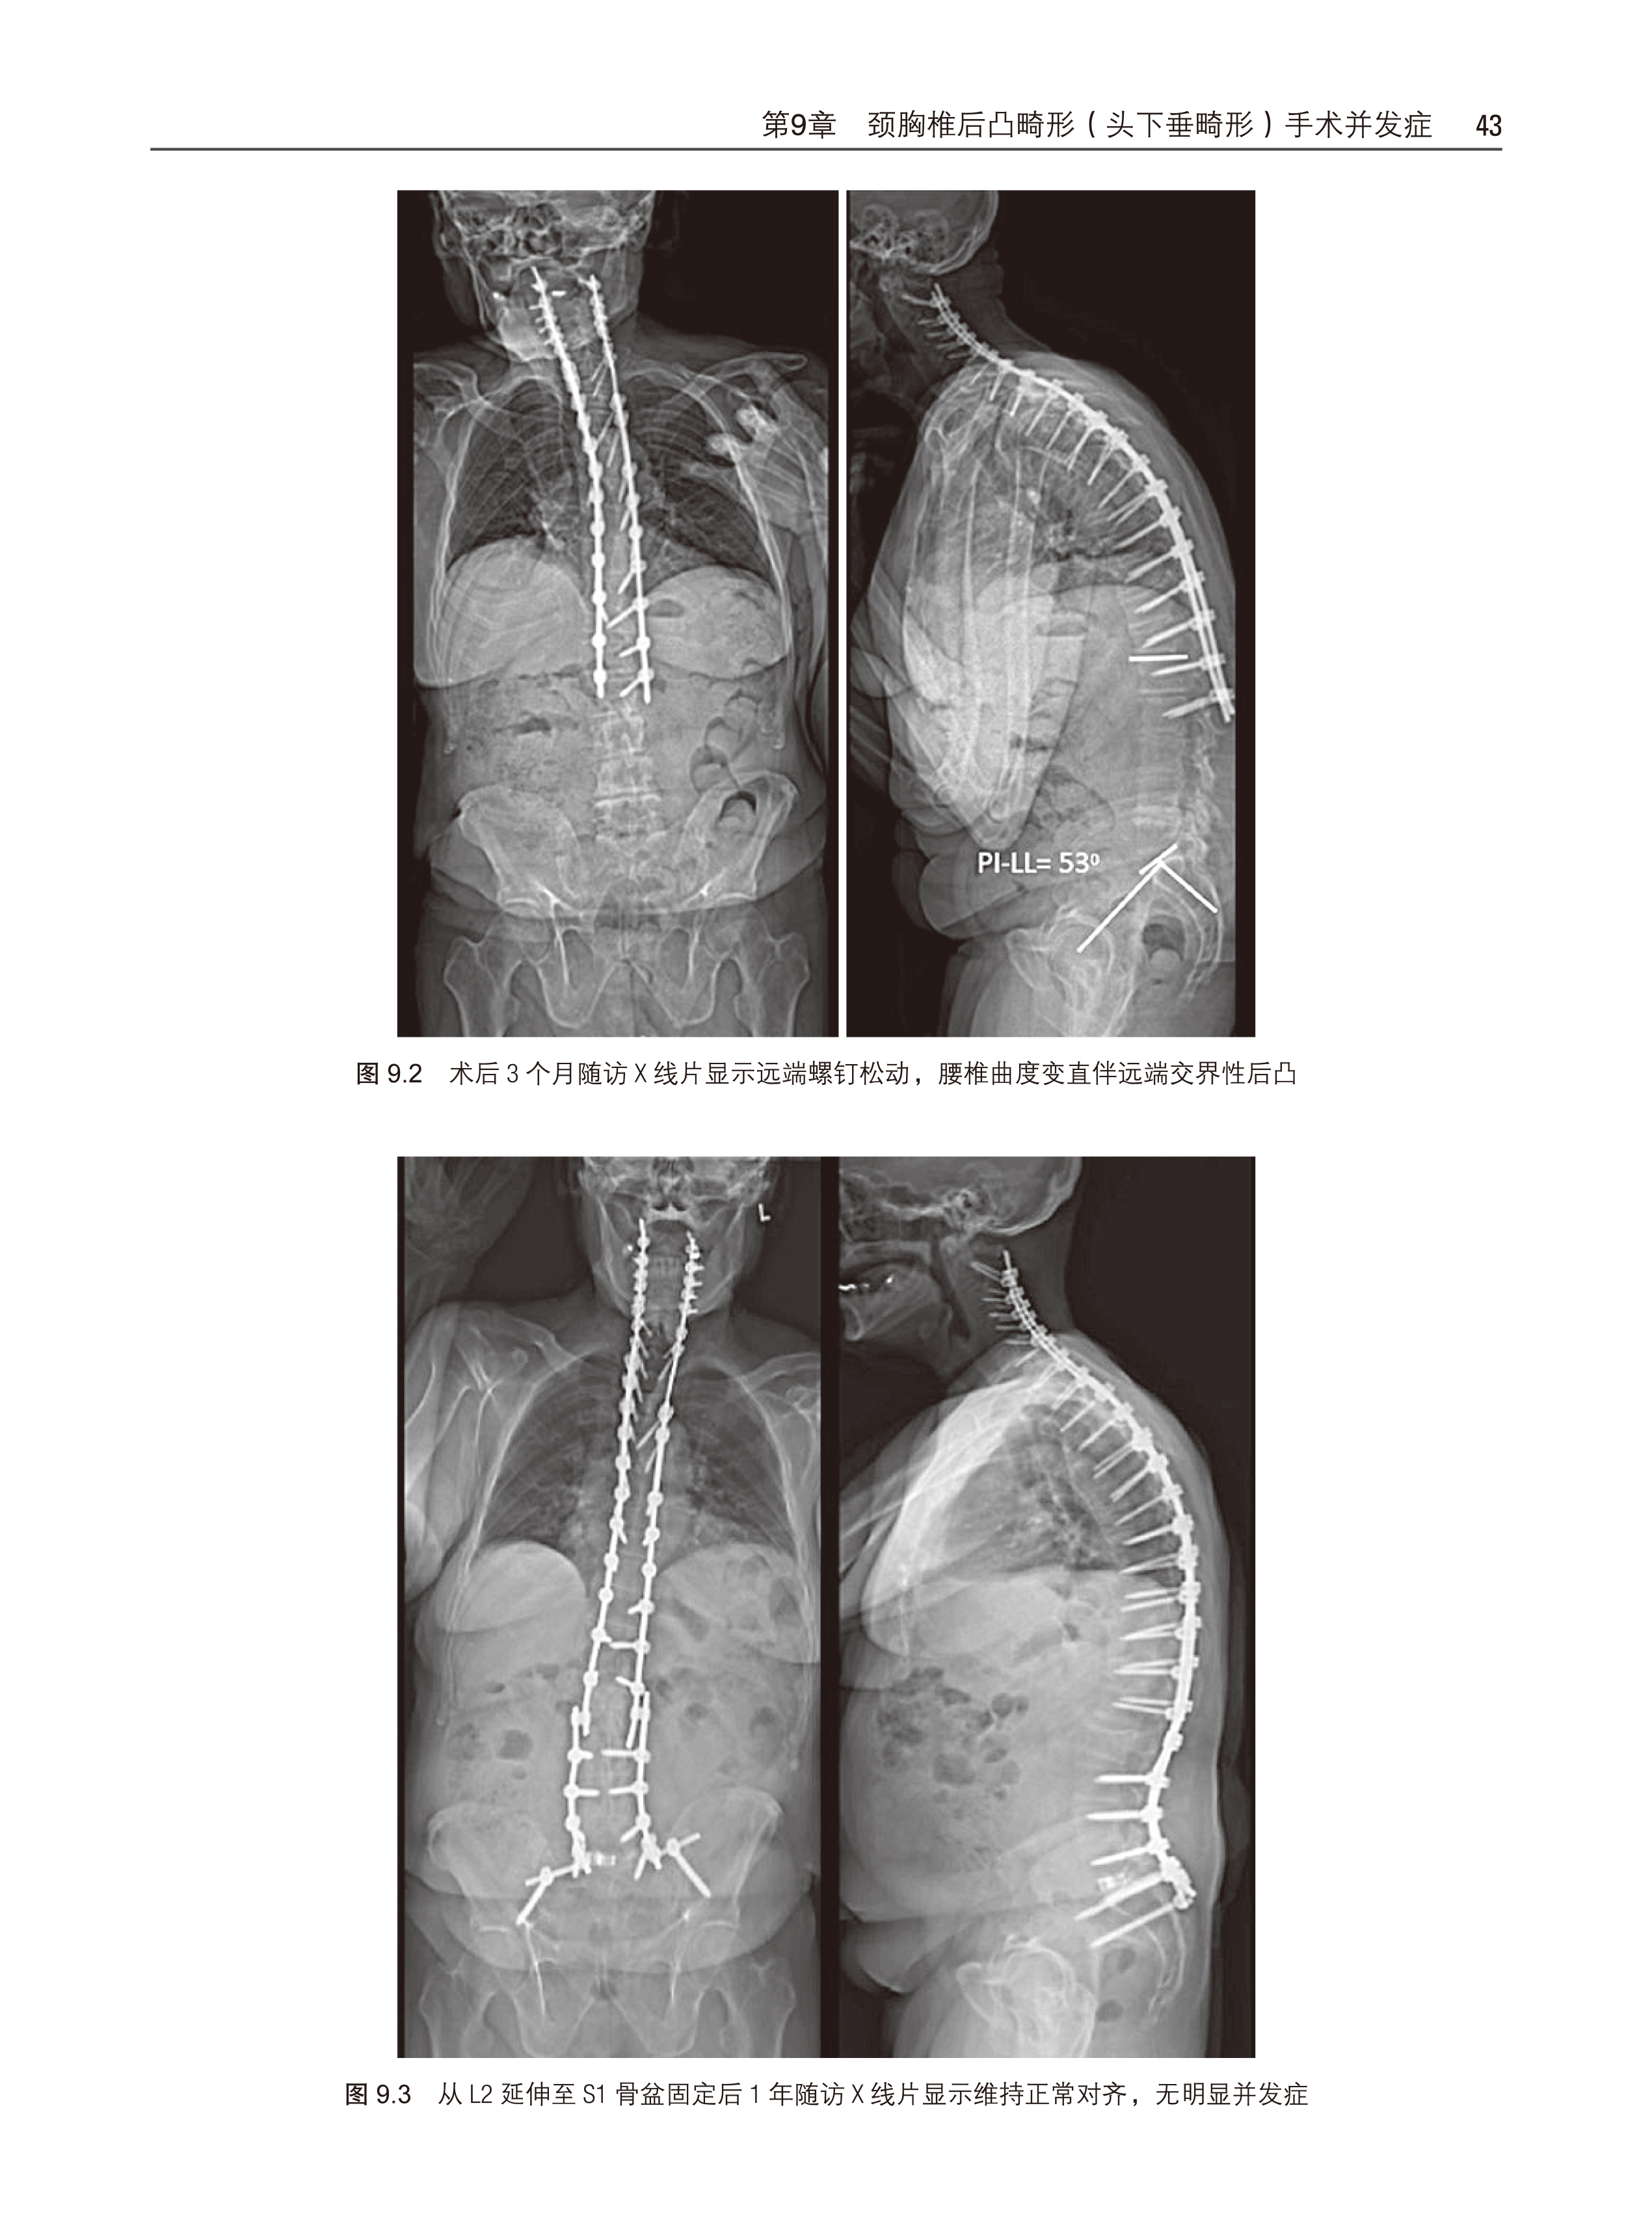

第 9 章 颈胸椎后凸畸形(头下垂畸形)手术并发症 41